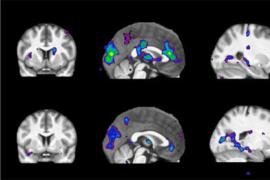

Когда речь идет о разработке новых способов диагностики болезни Альцгеймера, ученые в первую очередь сосредотачивают свое внимание на структуре головного мозга. Однако исследователи из Университета Тель-Авива (Tel Aviv University), Израиль, убеждены, что исследовать необходимо не структуру, а метаболизм головного мозга.

«На самых ранних стадиях болезни, задолго до появления первых внешних симптомов, в метаболических процессах головного мозга происходят первые изменения, — пишет в журнале Neurobiology of Aging автор исследования Шири Стемплер (Shiri Stempler) с медицинского факультета университета. — Поэтому мы разработали модель, предсказывающую развитие болезни Альцгеймера по определенным биомаркерам, которые можно получить с помощью обычного анализа крови. Точность предсказания составит до 90 процентов».

Исследователи обратили свое внимание на гиппокамп — структуру головного мозга, которая отвечает за память и обучение. Именно эта область наиболее поражается при прогрессировании болезни Альцгеймера. Ученые проанализировали метаболические гены, обнаруженные в нейронах гиппокампа и окружающей ткани, и из 1,5 тысячи генов отобрали 50 генов, претерпевающих наиболее характерные изменения. После этого ученые сравнили характеристики этого набора генов у здоровых людей, пациентов с болезнью Альцгеймера и приматов (шимпанзе и макак резус) и выяснили, что во всех группах, кроме больных пациентов, количество этих генов более-менее стабильно. Тогда как у пациентов с болезнью Альцгеймера этих генов либо заметно больше, либо ощутимо меньше. На основе этого анализа была создана модель, которая расценивает любые отклонения в количестве этих генов как сигнал о начале заболевания.

Теперь ученые намерены установить, какие биомаркеры крови свидетельствуют об этих метаболических нарушениях, чтобы диагностировать раннюю стадию заболевания можно было с помощью обычного анализа крови. Ученые надеются, что их исследование поможет не только в диагностике, но и в лечении болезни Альцгеймера. Ведь вопрос о том, являются ли метаболические нарушения в мозге причиной или следствием заболевания, до сих пор остается открытым.